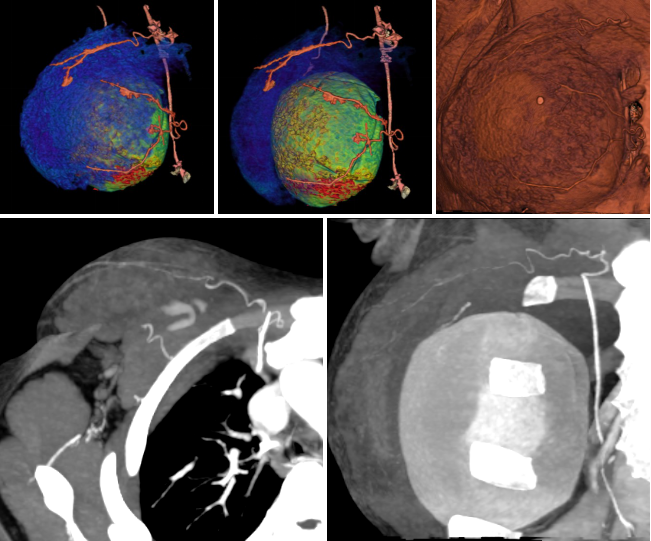

病例一 女,71歲,反復(fù)發(fā)作心慌、 胸悶、 出汗,血糖2 . 56 mmol/ L。

免疫組化:

CEA(-),CD31:血管內(nèi)皮細(xì)胞(+),Ki67:約1%瘤細(xì)胞陽(yáng)性,CK8(+),CK19(+),S yn(+),CgA(+)。

動(dòng)脈期可見(jiàn)胰腺體尾部腫瘤明顯強(qiáng)化,CT-MIP圖可見(jiàn)供腫瘤血血管,VR圖像可清晰顯示腫瘤的供血血管以及與周圍組織的關(guān)系。 術(shù)后結(jié)果為胰腺體尾部胰島素瘤。